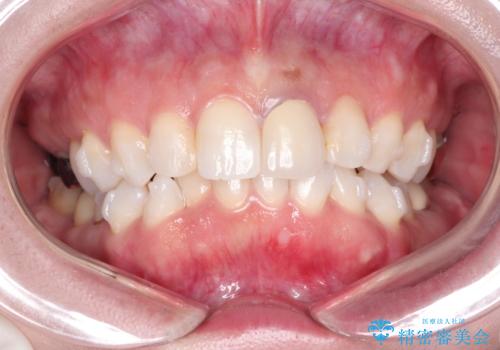

口元をさげたい ワイヤーによる抜歯矯正

- 口元が出てるのが気になるとのことで来院されました。

上下左右前から4番目の歯を抜歯して前歯を後方に下げて、口元を下げる計画としました。

口元を大きく改善したい場合は抜歯が必要となることが多いです。